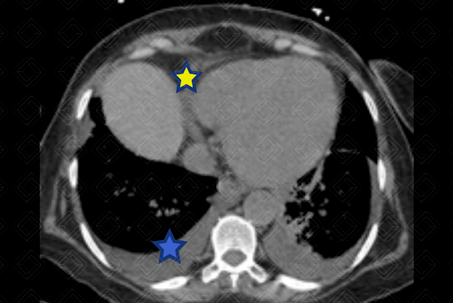

Texto alternativo para a imagem Figura 2. Créditos: Dra. Elazir Mota - Rio de Janeiro/RJ

Descrição das figuras 1, 2 e 3: Tomografia computadorizada de tórax. Espessamento liso dos septos interlobulares (setas vermelhas) associado a discretas áreas em vidro fosco na base pulmonar esquerda (seta preta), moderado derrame pleural bilateral (asterisco azul), derrame pericárdico (asterisco amarelo) e cardiomegalia. O conjunto de achados é sugestivo de congestão pulmonar.

• Tomografia computadorizada de tórax: Opacidades em vidro fosco, espessamento dos septos interlobulares, espessamento peribroncovascular, pavimentação em mosaico, aumento do calibre vascular, consolidações e nódulos de espaço aéreo (como nas figuras acima).